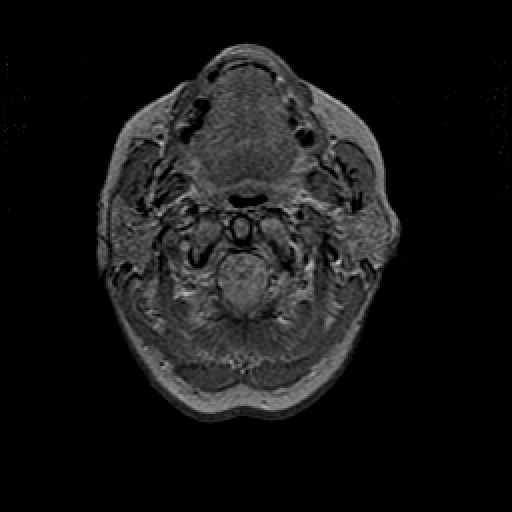

Proton density-weighted structural MR: Slice 2

Slice 2